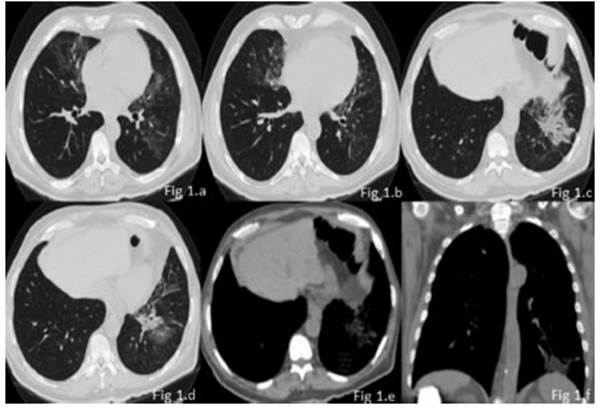

64-year-old male patient, university teacher, with history of insulin-dependent type I diabetes and chronic constipation, and without history of smoking. The patient was admitted to our institution with fever associated with asthenia, myalgia and arthralgia of 10 days of evolution. Subsequently, he had generalized cephalea and chronic cough. Given the current epidemiological context, the patient was tested for COVID-19 on two occasions, with negative results. Physical examination: BP 140/80; HR 85 lpm, BR 28 rpm, SatO2 94% aa, temperature 37.5 °C. He showed good ventilatory mechanics, and the auscultation identified fine crepitant rales in the left pulmonary base. Lab tests, cultures and specific serology were requested: hemoglobin, 8.9 mg-dl, PCR 27.8, negative hemocultures, negative urine cultures, negative sputum, negative galactomannan. A chest radiography was performed initially, showing a left basal consolidation; so, the patient began antibiotic treatment with azithromycin-ceftriaxone for 5 days, and then the regimen was modified and the patient continued with piperacillin-tazobactam because he had persistent fever. Due to persistent fever and lack of clinical response to treatment, a high-resolution chest tomography was performed, and it showed a spiculated, heterogenous lung mass with fibro-retractable bands and intralesional foci with negative density (fat density), located in the anterior and lateral segment of the left lower lobe. The mass was associated with patchy areas with increased interstitial-alveolar density, in ground glass opacity with geographic borders, with mild interlobular septal thickening (crazy paving pattern), in middle lobe, lingula and left lower lobe, with fine cylindrical bronchiectasis in the lingula.

Absence of adenopathies and pleural effusion (Figure 1).